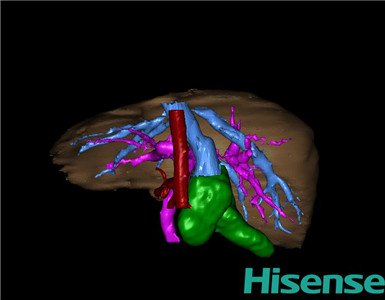

CT结果输入海信CAS系统后行3D重建及手术规划后,于2015-11-18全麻下行“胆总管囊肿切除+胆囊切除+胆总管-空肠吻合术”手术治疗:

将0.625mm双源薄层CT资料的静脉期和动脉期Dicom格式文件导入海信CAS系统。

通过调节窗宽窗位调整CT序号,对肝实质,胆囊,胆总管,下腔静脉,肝动脉、门静脉及肝静脉等进行三维重建;系统自动计算肝脏体积。

术前手术方案的规划。

术前三维重建:

重建图片